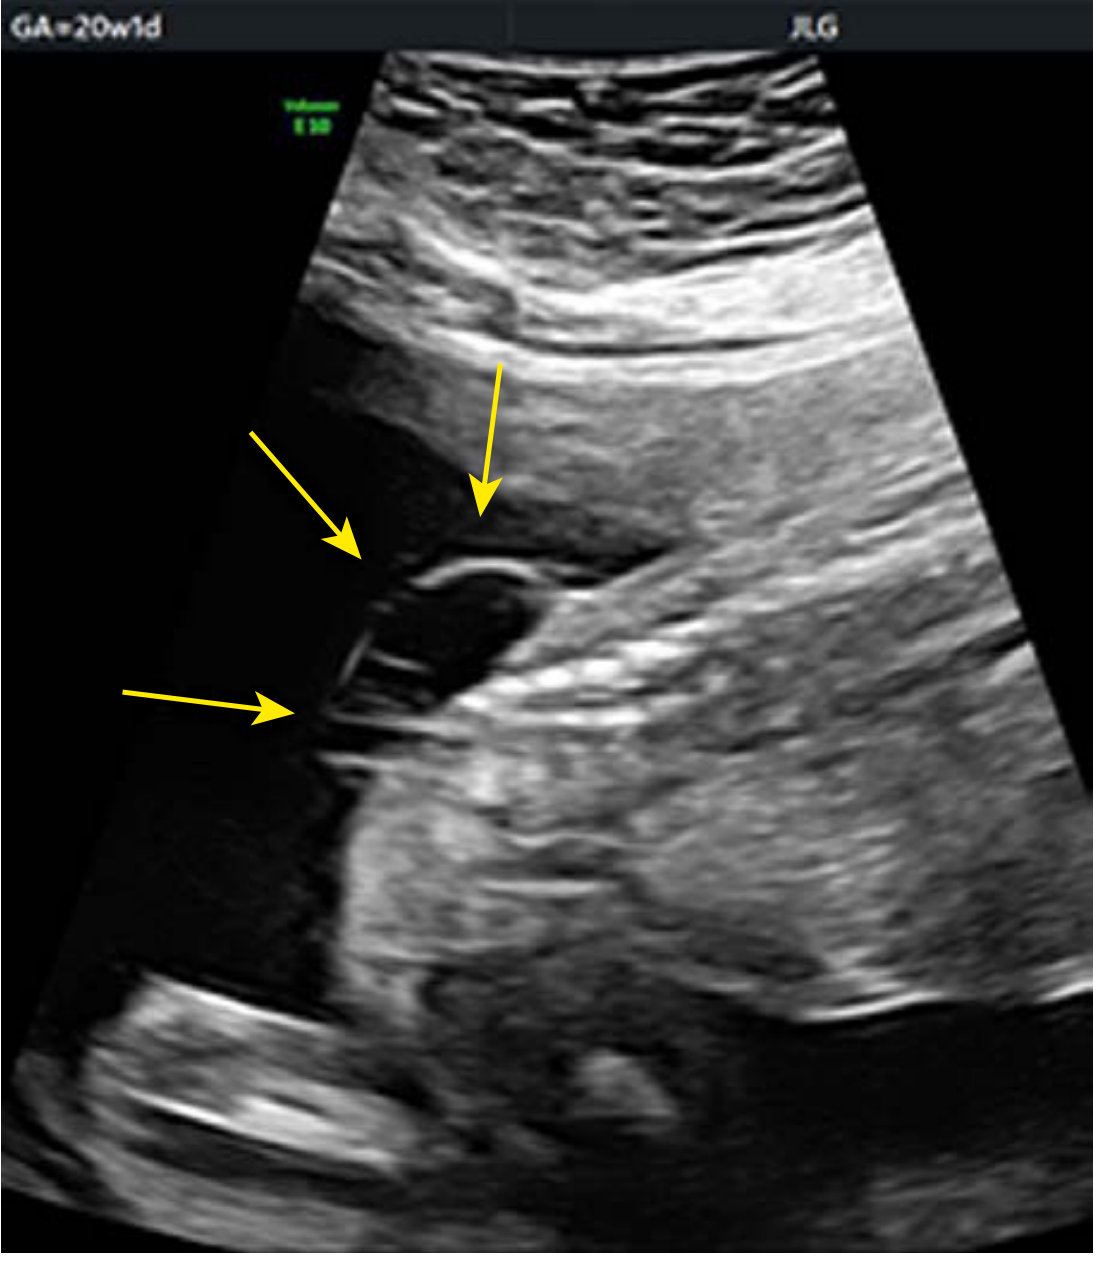

Myelomeningocele, sagittal ultrasound at 20 weeks

Sagittal ultrasound at 20 weeks showing disruption of posterior spinal elements with overlying cystic mass, consistent with myelomeningocele.

• Sagittal: Defect in the dorsal spine with overlying cystic mass

• Axial: V- or U-shaped splaying of posterior vertebral elements

• Coronal: Splayed posterior elements with midline defect